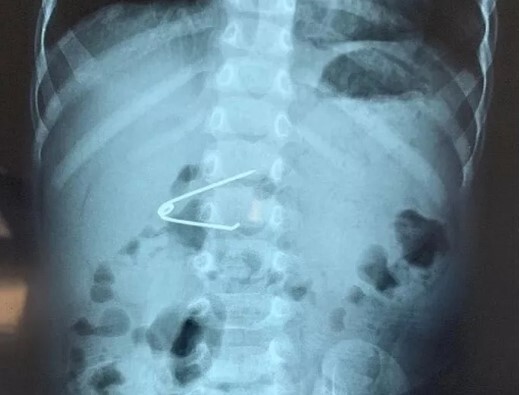

Được biết, bệnh nhi là con của vợ chồng chị V.T.T. ở Hà Nội, chào đời tại Bệnh viện Phụ sản Hà Nội khi mới 26 tuần. Sau khi ra đời, bé bị suy hô hấp rất nặng phải thở máy và các bác sĩ đã phát hiện ống động mạch của trẻ chưa đóng lại được. Mặc dù các bác sĩ đã dùng thuốc để ống động mạch của bé tự đóng lại nhưng 3 lần đều thất bại.

Sau đó, Bệnh viện Phụ sản Hà Nội quyết định chuyển bệnh nhi sang Bệnh viện Tim Hà Nội để các bác sĩ chuyên khoa tim mạch phẫu thuật. Tiếp nhận bệnh nhi, các bác sĩ Bệnh viện Tim Hà Nội đã hội chẩn xác định đây là một trường hợp phức tạp, có nhiều nguy cơ do trẻ quá nhỏ, thiếu tháng và nhẹ cân. Do đó, các bác sĩ quyết định tiến hành phẫu thuật theo phương pháp cắt, khâu ống động mạch.